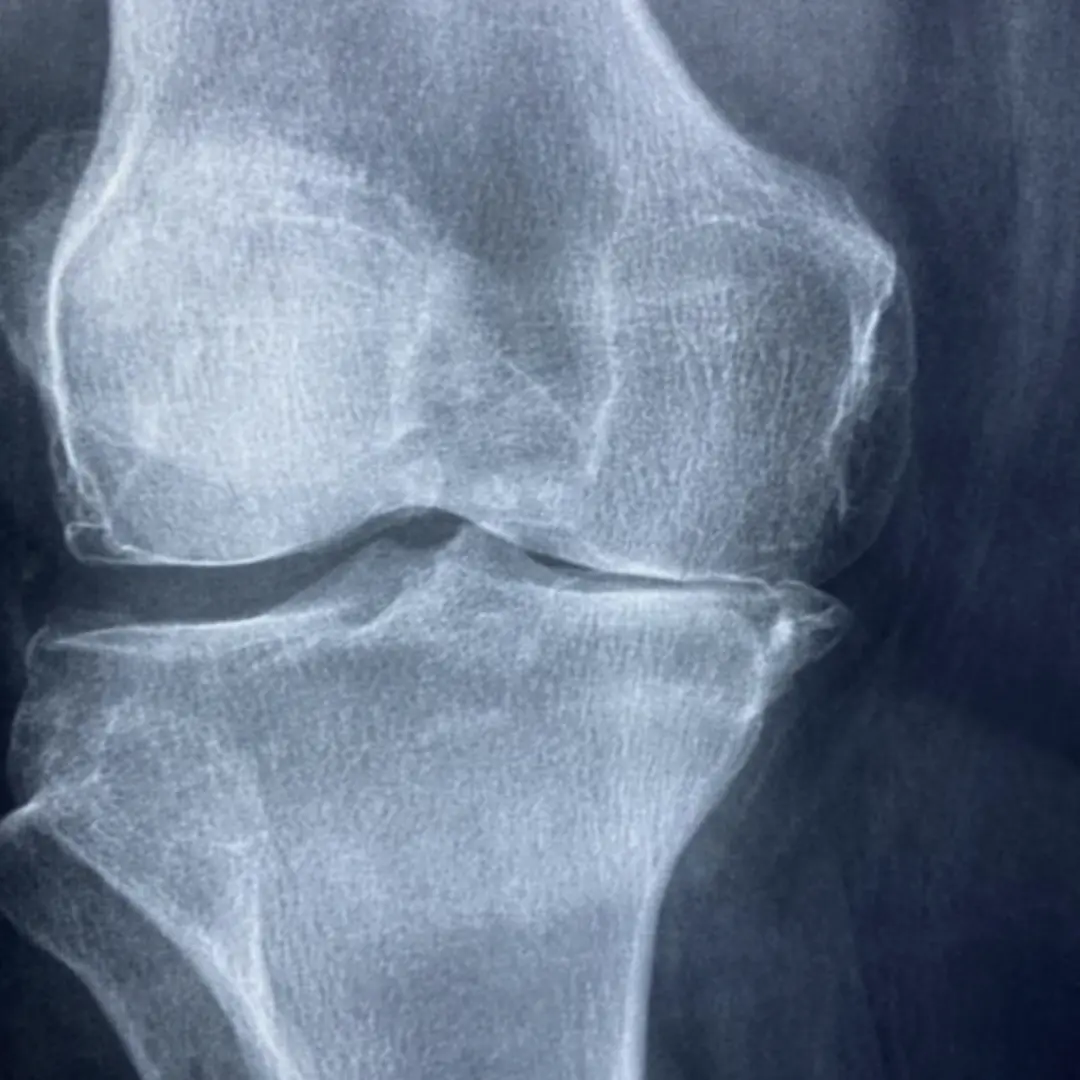

시간이 멈춘 듯 뻣뻣하고 삐걱거리는 관절, 혹시 닳아버린 연골 때문은 아닐까요? 걸을 때마다 느껴지는 불편함, 일상생활의 활력까지 앗아가는 관절 통증! 콘드로이친이 도움이 될 수 있습니다.

콘드로이친은 우리 몸, 특히 연골 조직에 자연적으로 존재하는 중요한 물질이에요. 황산콘드로이친이 주를 이루며, 글루코사민과 함께 연골의 주요 구성 성분으로 작용하지요. 이 특별한 물질은 연골에 수분을 공급하고 탄력성을 유지하는 데 핵심적인 역할을 수행해요. 마치 스펀지처럼 물을 머금어 연골이 외부 충격으로부터 관절을 보호하고 부드럽게 움직일 수 있도록 돕는 것이 바로 콘드로이친의 중요한 기능 중 하나예요.

나이가 들수록 체내 콘드로이친 생성량이 감소하면서 연골 손상과 퇴행성 관절염 발생 위험이 증가할 수 있어요. 따라서 외부로부터 콘드로이친을 보충해 주는 것이 관절 건강 관리에 중요한 의미를 가질 수 있지요. 콘드로이친은 주로 상어, 소 등의 연골에서 추출되며, 다양한 건강기능식품 형태로 섭취할 수 있도록 가공되어 판매되고 있어요. 단순히 연골의 구성 성분이라는 점을 넘어, 연골 보호 및 재생, 염증 완화 등 다양한 생리 활성 기능을 수행하는 매력적인 물질이라고 할 수 있어요.

콘드로이친은 단순히 연골의 구성 성분일 뿐만 아니라, 다양한 효능을 통해 관절 건강에 긍정적인 영향을 미치는 것으로 알려져 있어요. 가장 대표적인 효능은 관절염 증상 완화예요.

콘드로이친은 연골 손상을 억제하고 연골 세포의 생성을 촉진하여 관절 통증 감소와 기능 개선에 도움을 줄 수 있어요. 특히 퇴행성 관절염 환자들에게 꾸준한 섭취를 통해 증상 완화 효과가 나타나는 연구 결과들이 보고되고 있지요.